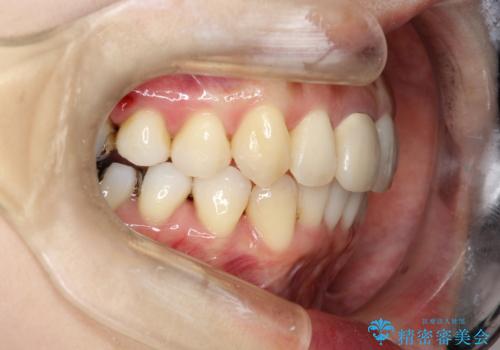

上下のガタガタのマウスピースによる非抜歯矯正

- 上下のがたつきを主訴に来院された患者様です。

上下の前歯と奥歯にがたつきがありました。

上下の奥歯を後方に移動させるのと、歯と歯の間をわずかに削ることでスペースを作り、歯を並べる計画としました。

インビザラインにて治療を行いました。

比較的がたがたの度合いが大きかったですが、しっかりとマウスピースを使用していただけたので、順調に治療を終えることができました。